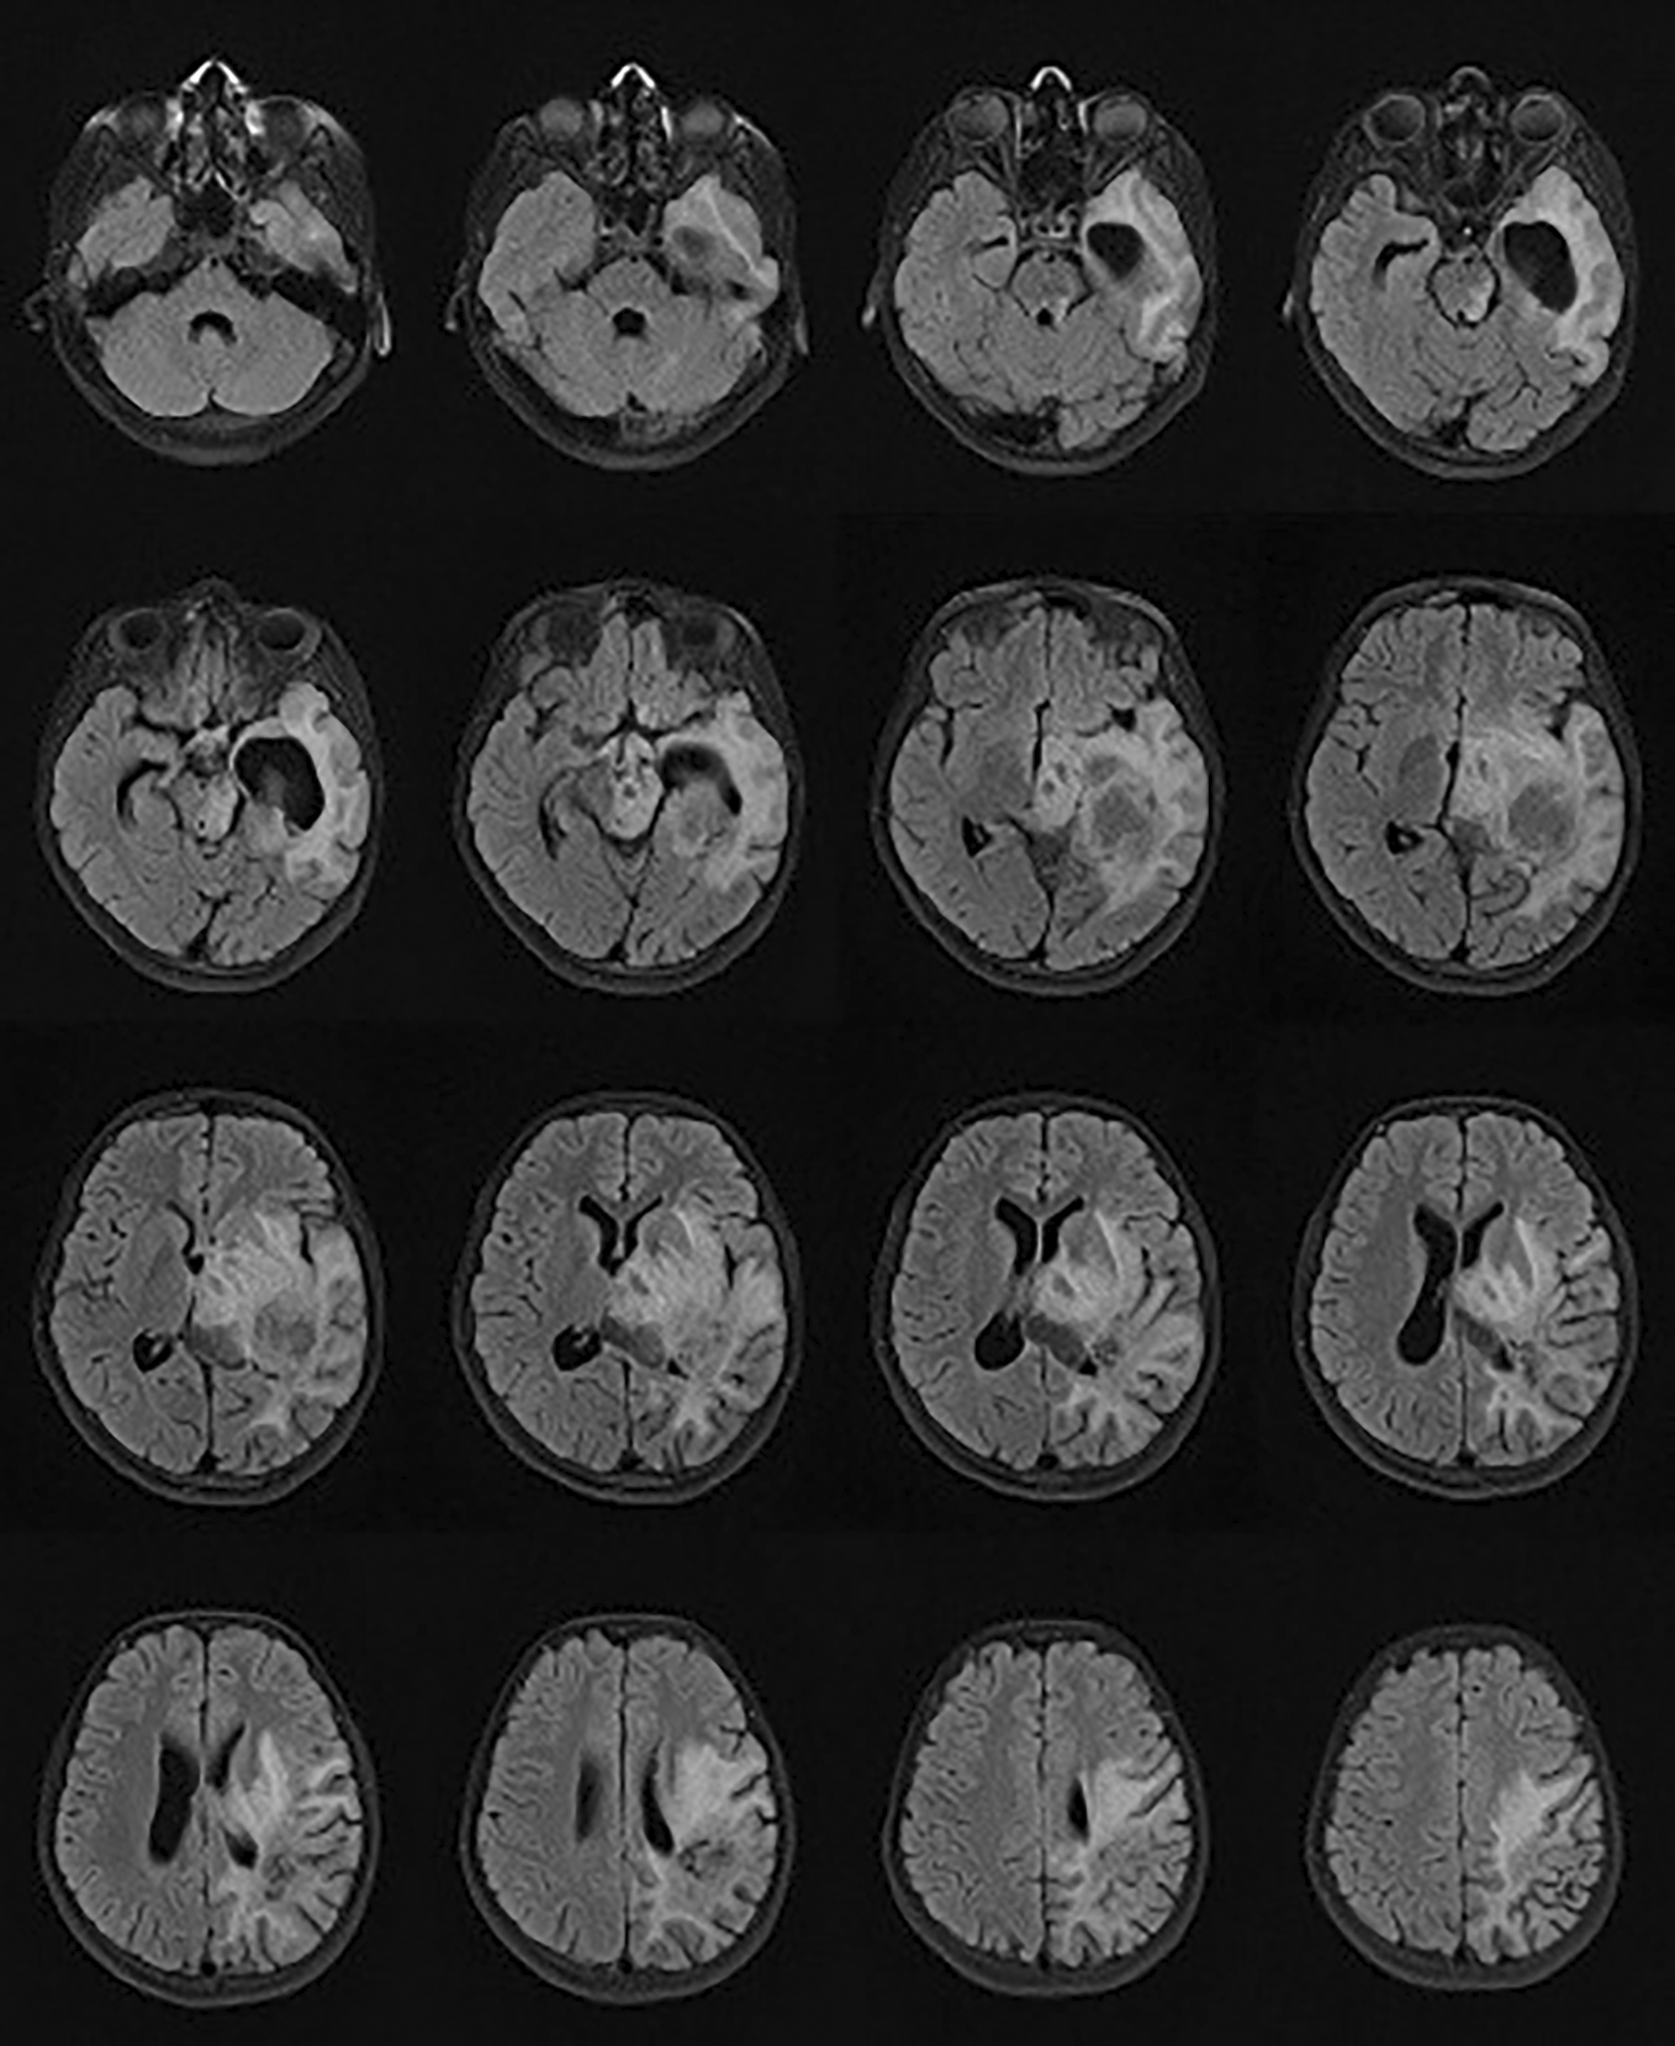

Initial evaluation revealed a Glasgow Coma Scale score of E4V5M6. The neurological examination revealed right-sided hemiparesis (3/5 strength) and bilateral papilledema. Fundoscopy confirmed signs of increased intracranial pressure (ICP). A series of neuroimaging studies, including a non-contrast head CT and a contrast-enhanced brain MRI, demonstrated a left temporoparietal mass with calcifications, perifocal edema, and a midline shift greater than 5 mm to the right. Preoperative brain MRI demonstrated a left temporoparietal mass with associated edema and a rightward midline shift, as shown in Figure 4. Based on clinical and radiological findings, the differential diagnosis included a supratentorial space-occupying lesion (SOL), with consideration of high-grade glioma, PNET, or pleomorphic xanthoastrocytoma.

This case illustrates the intraoperative integration of intravenous magnesium sulfate as an adjuvant to propofol-based TIVA during pediatric glioma resection with suspected raised ICP, emphasizing individualized cerebral physiology rather than relying solely on conventional fixed-target paradigms. Preoperative magnetic resonance imaging (MRI) demonstrated a left temporoparietal mass with edema and midline shift, providing pathophysiological context for the patient’s elevated intracranial pressure ( Figure 4). Magnesium infusion contributed to excellent intraoperative brain relaxation, stable systemic hemodynamics, and markedly reduced requirements for rescue opioids and neuromuscular blockers, supporting an early, non-delayed recovery trajectory. Importantly, the real-time use of optic nerve sheath diameter trends and transcranial Doppler to target MCA flow dynamics enabled bedside, physiology-concordant titration of ICP surrogates and cerebral perfusion conditions without invasive monitors, providing a pragmatic route to “personalized ICP-CPP surrogate management” during neuro-oncologic surgery in resource-limited pediatric settings. Directional improvement in ultrasound-derived ICP surrogates following MgSO4 administration is summarized in Table 2, emphasizing trend-based rather than absolute numeric interpretation.